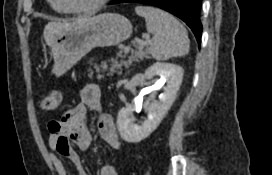

Мультиспиральная компьютерная томография почек и мочевыводящих путей  является высокоинформативным методом исследования, основанном на использовании воздействия рентгеновских лучей на органы и ткани человека. Методика предусматривает послойное сканирование области почек, мочевыводящих путей и получение снимков исследуемой области в мельчайших подробностях.

Для улучшения визуализации патологических очагов (различных кист или новообразований) в некоторых случаях дополнительно применяется контрастное усиление. Для этого пациенту внутривенно вводится йодсодержащее контрастное вещество, которое накапливается в патологически измененных участках и вызывает их яркое контрастирование на фоне здоровых тканей.

МСКТ почек и мочевыводящих путей с контрастированием позволяет выявить опухолевые образования на ранних стадиях, отличить доброкачественную опухоль от злокачественной, определить размеры опухоли, точную локализацию и степень распространения в окружающие ткани. Компьютерная томография почек с внутривенным болюсным контрастированием необходима для определения тактики лечения и объема оперативного вмешательства.

В клинике «Доступная медицина» исследование проводится с помощью современных мультиспиральных томографов экспертного уровня TOSHIBA AQUILION, которые производят сканирование области почек в виде тончайших срезов с шагом от 0,5 мм, затем обрабатывают полученные данные и выдают трехмерные изображения отсканированной зоны.